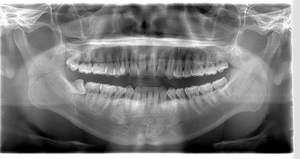

左下親知らずがたまに痛み、

できれば痛くなく抜きたい症例

- 抜歯前写真(レントゲン)

- 抜歯前写真(CT画像)

| 年齢 | 20代・女性 |

|---|---|

| 主訴 | 左下親知らずがたまに痛み、できれば痛くなく抜きたい |

| 親知らずの生え方 | 完全に埋まっている、横向きに生えている |

| 抜歯時間 | 50分 |

| 費用 | 約8,000円(保険診療、CT代含む) |

| 抜歯内容 | 左下親知らずが横向きになって半分埋まっている状態だったため、麻酔を行い、親知らずの奥の歯ぐきに切開をいれ、歯が囲んでいる骨を削り、歯の頭の部分を削って出し、その後根の部分に器具をかけて抜歯しました。 親知らずが一部神経に近い部分があったため、術後に麻痺が出る可能性がありました。このケースでは事前にCTを撮影し、歯の位置、根の方向、神経との距離を確認していたため、幸い麻痺が出ることはありませんでした。 術後1週間経過して糸取りをして治療は終了となりました。抜歯後3日間は腫れと痛みで大変だったが、糸取りをする頃には痛みも腫れも無くなったと患者さまも喜んでおられました。 |